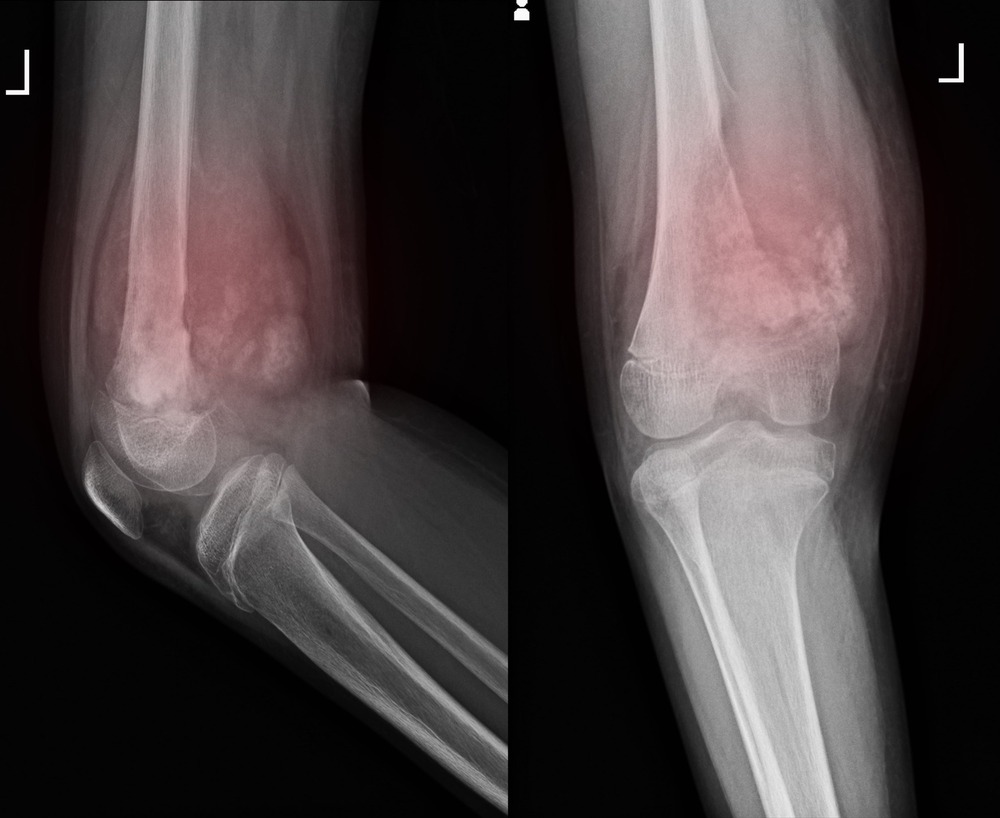

Assessment usually starts with a careful history and physical examination, then moves quickly to imaging. The goal is to understand the size of the mass, where it sits in relation to muscles, nerves, and vessels, and whether it looks like something that should be biopsied.5, 8

Common imaging includes ultrasound (often an early step for superficial lumps), and MRI or CT for deeper masses or for surgical planning. Imaging can suggest what a lump might be, but it cannot provide the final answer on its own.5, 8